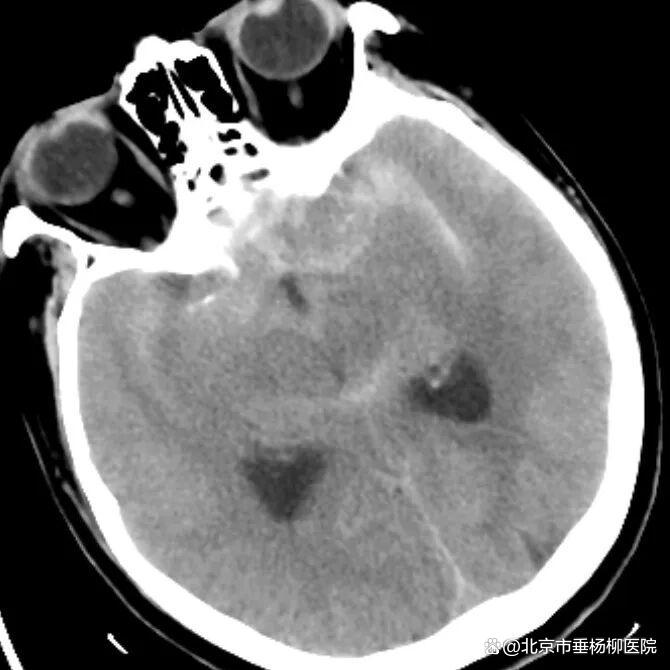

病例一为77岁女性患者,既往高血压病史。因“突发剧烈头痛伴恶心2天”前来清华大学附属垂杨柳医院急诊科就诊。头颅CT检查提示蛛网膜下腔出血,头颈动脉CTA提示右侧大脑中动脉M1段分叉处宽颈动脉瘤。神经外科脑血管病介入团队急诊为患者实施了全脑血管造影术(DSA),造影显示动脉瘤不规则,可见子囊,宽颈,主要累及下干。团队采取了支架辅助弹簧圈栓塞术,患者颅内“不定时炸弹”被成功拆除。动脉瘤达到致密栓塞,载瘤动脉通畅。住院半个月后顺利出院,无神经功能障碍。

▲头颅CT显示蛛网膜下腔出血